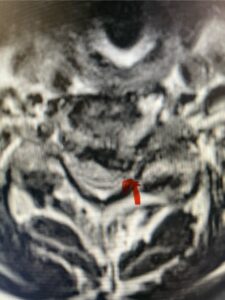

This 61-year-old female with a history of severe osteoporosis and a prior history of a laminectomy from l2-S1 with an L5-S1 instrumented fusion, presents with progressive low back pain and right lower extremity radiculopathy. MRI revealed a grade 1 L2-3 spondylolisthesis with severe stenosis mainly from severe right L2-3 facet joint hypertrophy which was compressing the right L3 descending nerve root. (Fig. 1). She had failed conservative management consisting of physical therapy and pain management with epidurals. She underwent an L1-3 revision laminectomy where we had to dissect a plane underneath the inferior aspect of the L2 lamina. We performed an instrumented fusion at L2-3 with special hydroxyapatite-coated screws to improve fixation to surrounding bone given here severe osteoporosis (Fig. 2) This worked out well and the patient had an uneventful recovery with relief of her leg pain.

Figures 1a: Sagittal and axial T2-weighted lumbar MRIs demonstrating a grade 1 L2-3 spondylolisthesis (red arrow) with severe stenosis secondary to right L2-3 facet hypertrophy (red arrow).

Fig 1b: Note the left L2-3 facet joint (blue arrow) is normal in size compared to the right (red arrow)